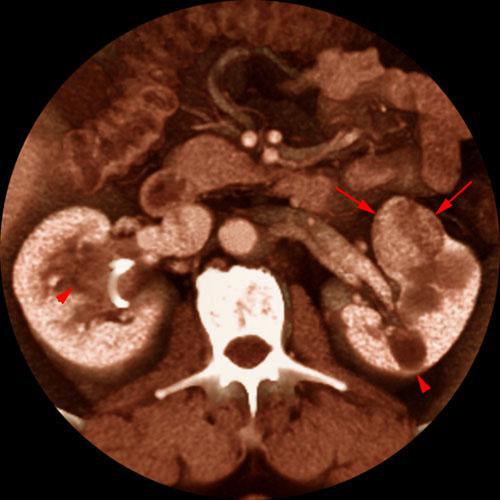

Quiste renal multitabicado e hipernefroma

VR seccional. Visión axial caudal. Lesión nodular sólida en valva anterior del riñón izquierdo (flechas) altamente sugestiva de hipernefroma. Lesiónes quísticas asociadas (puntas de flecha) en ambos riñones, una de ellas multitabicada